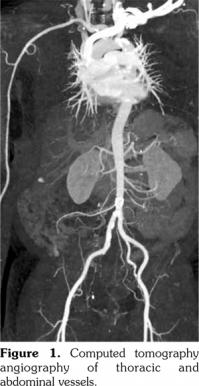

A 56-year-old male patient presented with high grade fever and headache for a month associated with proximal myalgias, right ankle synovitis, and bilateral orchitis. His general examination was remarkable for the thickened right superficial temporal artery with scalp tenderness. Lab tests revealed an erythrocyte sedimentation rate of 112 mm/at the end of 1st hour, a C-reactive protein level of 396.3 (<5) mg/L, normal liver and kidney functions, and an unremarkable urine microscopy. His anti- nuclear antibodies, cytoplasmic-anti-neutrophil cytoplasmic antibodies, perinuclear-anti- neutrophil cytoplasmic antibodies, and hepatitis serology were all negative. Ultrasound Doppler of the testes revealed increased vascularity suggestive of orchitis and funiculitis in both testes. Computed tomography angiography of thoracic and abdominal vessels revealed no evidence of vessel aneurysms or stenosis (Figure 1). The temporal artery biopsy (TAB) revealed dense mixed inflammatory infiltrate consisting predominantly of lymphocytes and histiocytes involving the tunica adventitia, and the media with an extension into the intima and near complete destruction of external elastic lamina and focal disruption of internal elastic lamina (Figure 2). There was no fibrinoid necrosis, leukocytoclasia or giant cells in the examined biopsy specimen. Patient was then treated with pulse intravenous methylprednisolone followed by oral steroids and methotrexate. Resolution of symptoms was noted over four weeks. Currently, after six months of follow-up, the patient is stable and on weekly subcutaneous methotrexate 20 mg along with prednisolone five mg/day. A written informed consent was obtained from the patient.

Narváez et al.(2) found peripheral arthritis in eight of their 73 patients (11%) with GCA, which was typically peripheral, distal, asymmetric, non- erosive, and temporary. Orchitis and epididymitis have been reported previously as the sole urological manifestations of GCA.(3) When the disease has atypical presentation, histological analysis of TAB biopsy specimen plays a key role in distinguishing GCA from non-GCA arteritides.(4) The TAB in our patient revealed panarteritis with a predominant lymphocytic and histiocytic infiltrate, which is consistent with the histological pattern of GCA.(5) Absence of significant leukocytoclasis, neutrophil/eosinophil infiltrate and fibrinoid necrosis argues against the alternative etiology such as polyarteritis nodosa and anti-neutrophil cytoplasmic antibodies vasculitis in our patient. Although giant cells were not visualized in the observed biopsy specimen, they are typically observed in only about half of the biopsy positive patients with GCA and are not mandatory for diagnosis.(6)